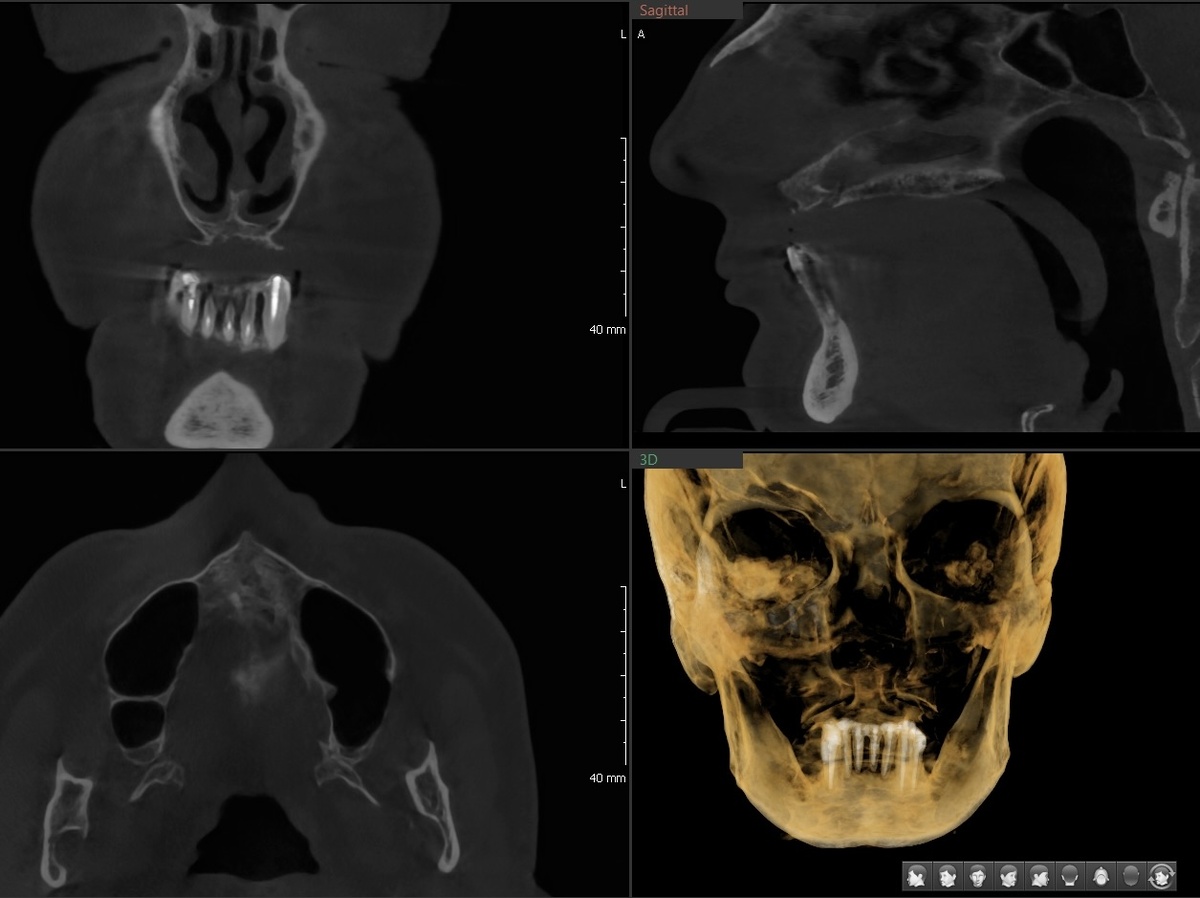

На нижней челюсти сохранились фронтальные зубы:

Нижняя челюсть

"Сохранились" - громко сказано, конечно. Кости нет, держатся на честном слове:

КТ нижней челюсти до

Спасать такое - не вариант точно. Не перспективно. И так всё, что можно было из ситуации "выжать", кто-то выжал - шинирование, например, было выполнено.